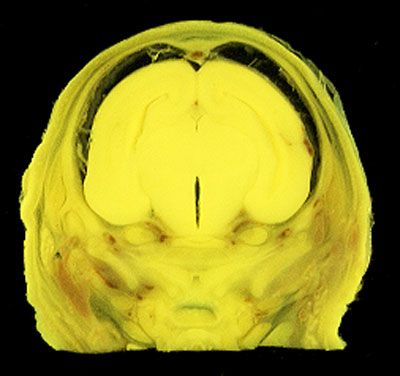

NORMAL APPEARANCE OF THE BOUIN'S FLUID FIXED RAT HEAD

The images below show the normal appearance of Bouin's fluid fixed head sections in specimens at Day 21 of gestation (day mating observed = Day 0).

It is essential that both sides of each section is examined so that structures that exist is several sections can be visualised by the examiner in 3D.

Learning objective: Compare the diagrams with your own specimens and identify all of the structures that have been labelled.

Unlabelled Images